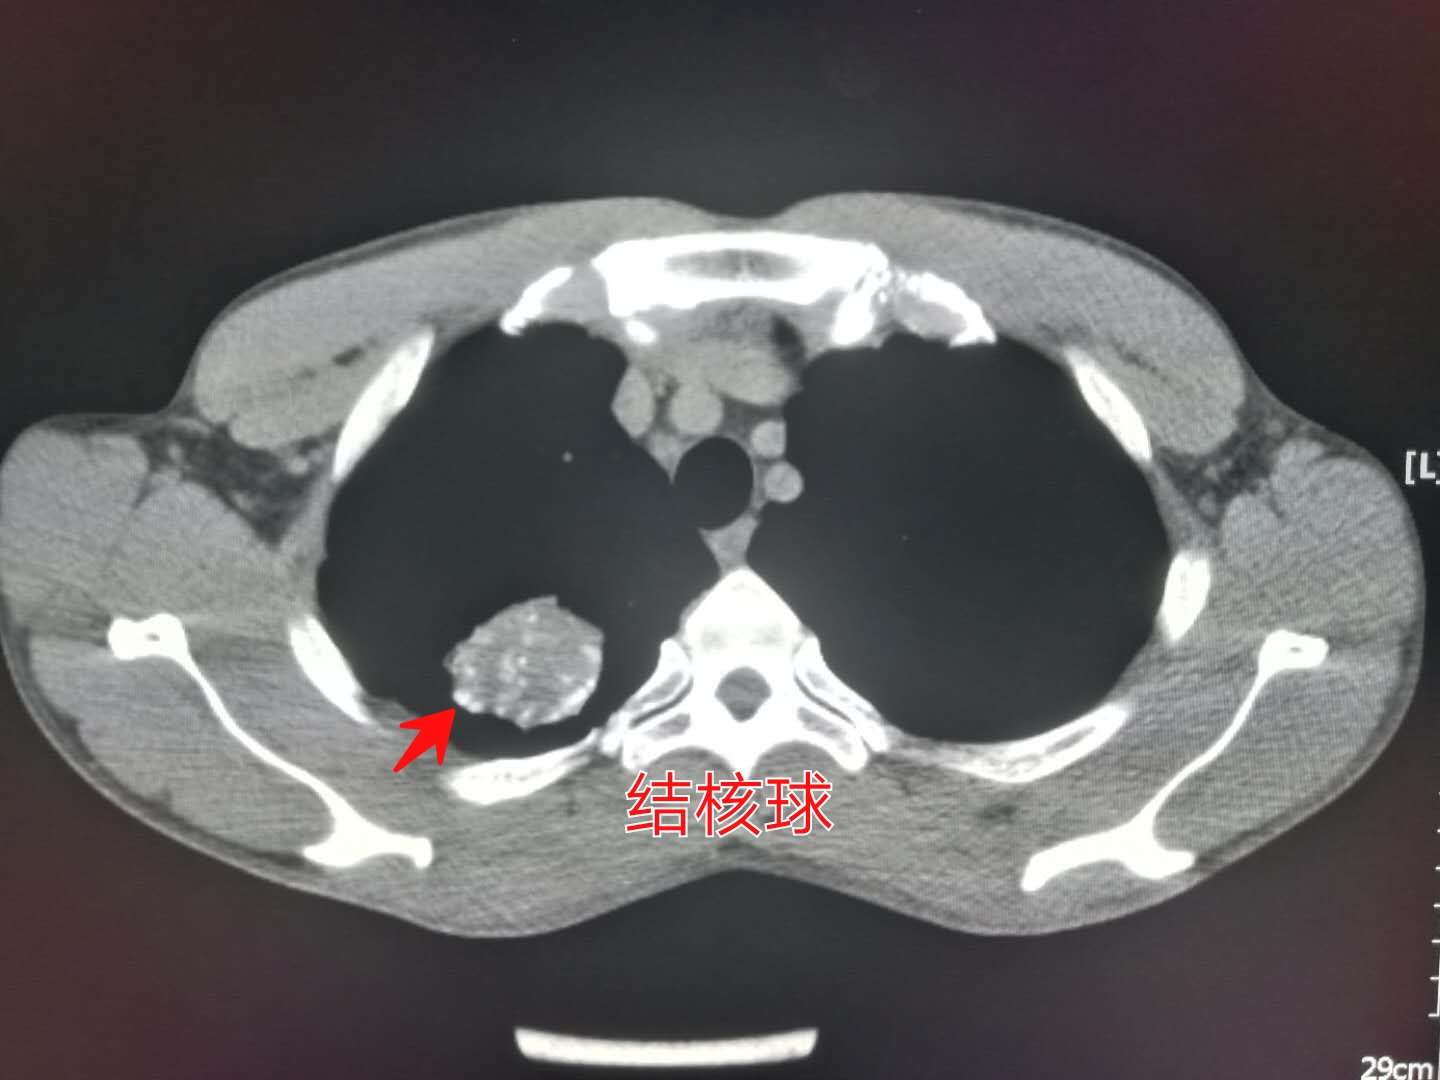

CT片上可以看到,右肺尖一个球形病灶,边界清晰,里面有多高斑点状的钙化,这个是典型的“结核球”。

视察他第一次的片子,在结核球的周围还有小斑片影和一些小结节(属于肺结核的卫星灶),本次已经基本吸收了,说明治疗有效。

我们从开篇第一张图中可以看出,小伙子的结核球属于孤立性病灶,伴有多发斑点状钙化,没有空洞,没有树芽征,也没有肺实变和磨玻璃密度影,气管壁没有增厚,说明不具备影像学的活动期表现。